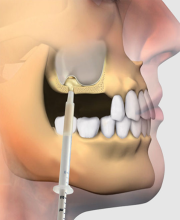

1. آمادهسازی محل جراحی: لثه باز میشود و ناحیه استخوان نمایان میشود.

2. کاشت ایمپلنت: پایه تیتانیومی (فیکسچر) ایمپلنت در استخوان باقیمانده قرار داده میشود.

3. بازسازی استخوان: نواحی فاقد استخوان یا ضعیف، با یکی از مواد پیوندی پر میشود (مثل آلوگرافت، زنوگرافت، یا بیومتریالهای سنتتیک).

4. استفاده از غشا در صورت نیاز: یک غشای مخصوص (غیر قابل جذب یا قابل جذب) روی ناحیه پیوند قرار داده میشود تا از نفوذ سلولهای بافت نرم جلوگیری کرده و فقط سلولهای استخوانساز وارد منطقه شوند.

5. بخیه و بسته شدن ناحیه: در پایان، محل جراحی بخیه میشود و مرحله ترمیم شروع میشود.